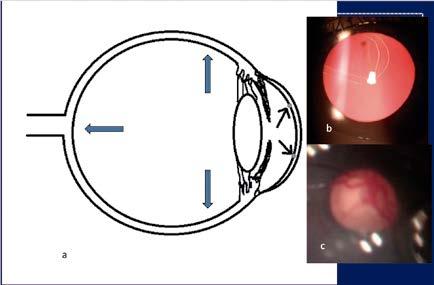

La expansión de los tejidos se manifiesta de las siguientes formas. En la córnea se producen roturas en la membrana de Descemet, conocidas como estrías de Haab, y también opacidades corneales. Esto causa lagrimeo excesivo, sensibilidad a la luz y blefarospasmo, típica triada de síntomas de glaucoma congénito. Además, el diámetro corneal y la longitud axial pueden aumentar significativamente, dando lugar al conocido ojo buftálmico. (Figura 1) El diámetro corneal de un recién nacido es de 9.5 a 10 mm. Un diámetro corneal de más de 10 mm en un recién nacido o más de 12 mm en un menor de 1 año de edad es sospechoso de glaucoma.

Figura1. El incremento de presión intraocular en ojos pediátricos puede producir una expansión de los tejidos intraoculares (a), con estrías de Haab (b) y excavación del nervio óptico.